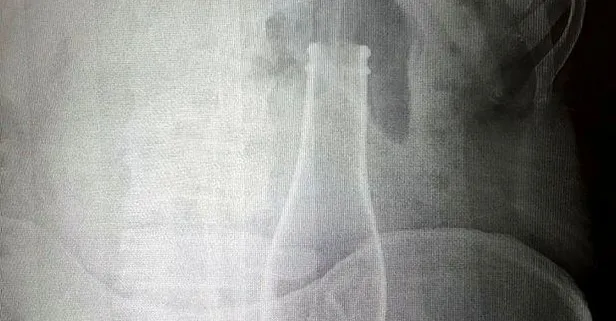

Karaman Eğitim ve Araştırma Hastanesi'ne, 28 Haziran Pazar gecesi gelen A.E., karın ağrısı şikayeti olduğunu söyledi. Bunun üzerine röntgen filmi çekilen gencin kalın bağırsağında şişe olduğu görüldü. Makattan girdiği belirlenen şişe, yaklaşık 1 saat süren ameliyatla çıkarıldı.